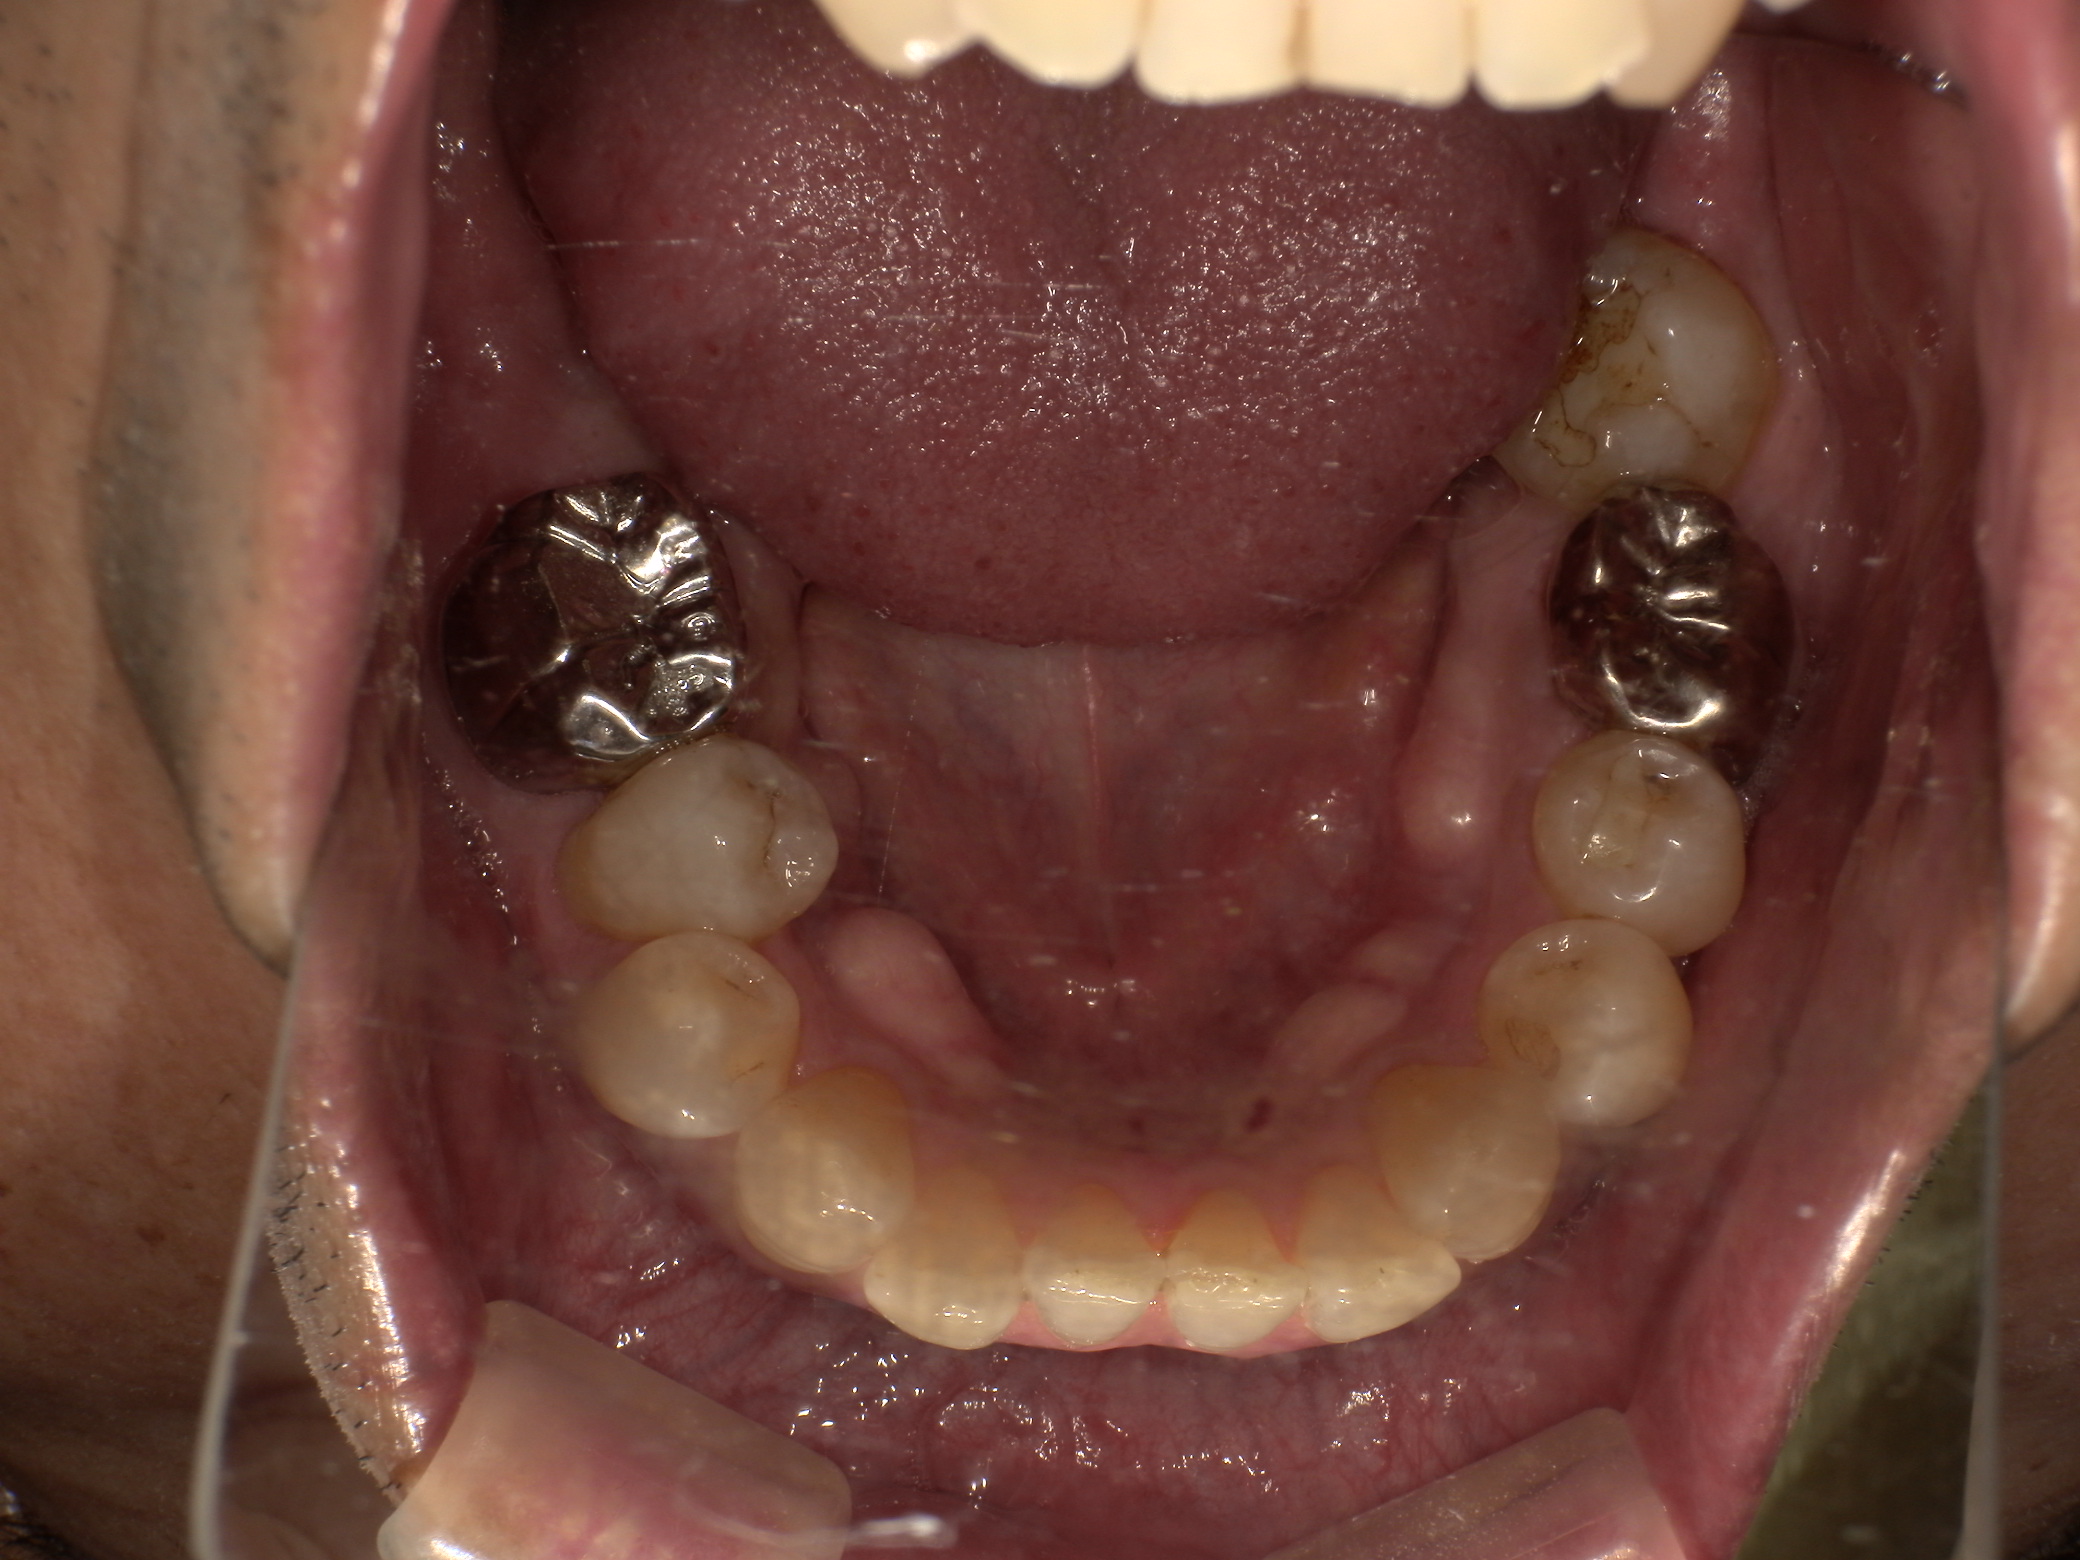

After

ソケットプリザベーション後、6ヶ月の治癒期間後にインプラントの埋入実施。

口腔内装着後